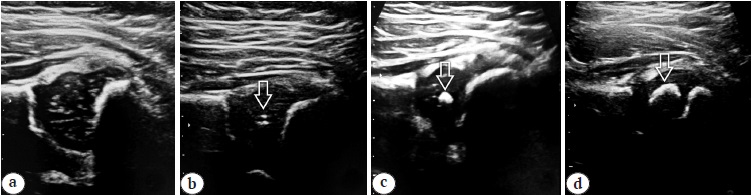

Один центр окостенения находится в ядре проксимального эпифиза головки бедренной кости, второй образуется в большом вертеле в более позднем возрасте — к 4 годам [24]. Стадии формирования ЯО проксимального эпифиза бедренной кости нами были обозначены следующим образом:

– 1-я стадия — ядро отсутствует (рис. 2 а);

– 2-я стадия — ядро-точка визуализируется в виде одного или нескольких точечных включений, склонных к слиянию, также эту стадию обозначают как намечающееся ЯО (рис. 2 b);

– 3-я стадия — ядро-пятно визуализируется в виде четкого округлого гиперэхогенного участка без акустической тени, диаметр до 4 мм (рис. 2 c);

– 4-я стадия — ядро-полумесяц, крупное ядро с дистальной акустической тенью (рис. 2 d).

Рис. 2. Сонографические стадии формирования ядра окостенения головки бедренной кости (отмечено стрелками): а — ядро не визуализируется; b — точечное ядро; c — ядро-пятно; d — ядро-полумесяц с акустической тенью / Fig. 2. Ultrasonographic stages of the formation of the secondary ossification center (SOC) of the femoral head (marked by arrows): a — the SOC is not visualized; b — point stage; c — spot stage; d — crescent stage with acoustic shadow

На 4-й стадии латеральные отделы окостеневшего ядра отражают ультразвуковые лучи, медиальные участки остаются в акустической тени, в результате чего крупное ЯО на сонограмме выглядит как полумесяц. Так как на данной стадии ядро имеет форму сплющенного в кранио-каудальном направлении эллипса, при УЗИ более корректным было бы говорить не о диаметре, а о высоте ЯО. Высота ядра на этой стадии больше 5 мм. С целью более точного вычисления размеров ядра и выявления асимметрии между правой и левой сторонами на этой стадии нами рекомендуется дополнительная оценка поперечных срезов головки бедренной кости со сравнением максимального поперечного размера ядер правой и левой сторон из переднего доступа в нейтральной позиции, так как при стандартном подходе из бокового доступа максимальный поперечный размер ядра измерить не представляется возможным [27].